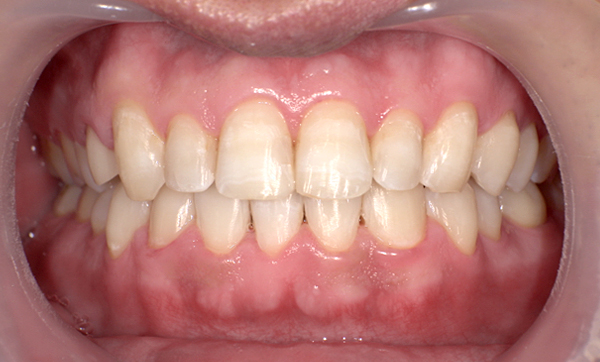

症例_008 「上下の前歯」症例

治療期間:13ヶ月金額:57万円+税40代女性捻転歯前歯のガタガタ

Before | After |